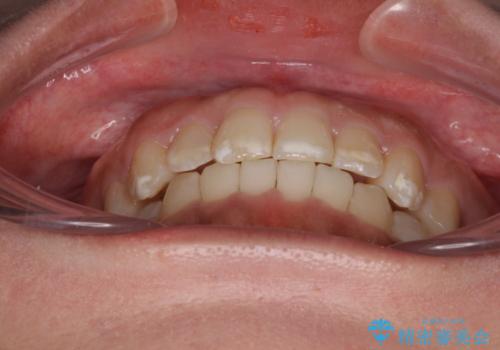

インビザライン・モデレートを用いて気になる前歯を短期間で矯正治療

- 8ヶ月

- 5-10回

インビザライン・モデレートは、製作できるアライナーの枚数に制限があるため、移動可能な量に限りがあるものの、インビザライン・ライトよりも枚数が多いため、幅広い症例に対応可能です。